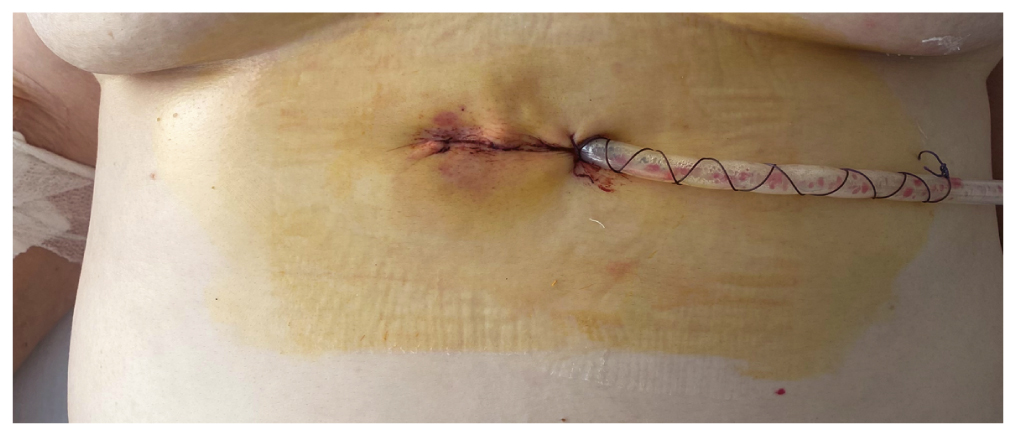

During the surgery, an instrument was used that was specifically developed for minimally invasive thoracoscopy (Fig. 6). The dissection of tissues was done using the ultrasound scalpel (Harmonic Ethicon). The surgical intervention was completed by the installation of the single-lumen draining tube with the diameter of 20 Fr into the aperture of the left half of the chest cavity, which was passed through the surgical wound (Fig. 7, 8).

Fig. 8. Thoracoscopic thymectomy from a uniportal subxiphoid approach. Appearance of the wound on the first postoperative day.